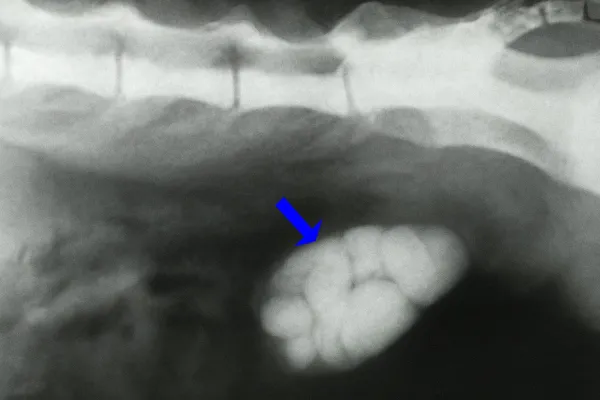

5. Cálculos renais

Os cálculos ou nefrólitos renais em gatos são depósitos duros de minerais que se formam dentro dos rins e podem causar danos graves ao órgão afetado. Embora os nefrólitos renais sejam menos frequentes que os de vesícula, também podem aparecer devido a alterações na concentração da urina ou em seu pH, a dietas com excesso de minerais, a baixa ingestão de água ou a predisposição genética.

Entre os felinos, os cálculos mais comuns são os de oxalato de cálcio, que são duros, não se dissolvem e predominam no rim, e os de estruvita, que contêm fosfato de amônico magnesiano e costumam se formar com mais frequência na bexiga.

Sintomas

Os cálculos renais podem provocar sintomas como dor abdominal ou lombar, hematúria, vômitos, micção frequente ou dificultosa, letargia e até anorexia.

Tratamento

O tratamento dos cálculos renais depende em grande medida do tipo de cálculo:

- Os cálculos de estruvita podem ser dissolvidos por meio de dieta renal;

- Os cálculos de oxalato de cálcio costumam requerer cirurgia, seja por nefrotomia ou ureterotomia em caso de obstrução grave do fluxo de urina. Em centros especializados, também pode ser realizada uma intervenção chamada litotrícia, que consiste na fragmentação dos cálculos por meio de laser ou ultrassom.

Além disso, é importante aumentar a hidratação do gato, controlar a dor e fornecer suporte renal nos casos em que a função do rim estiver gravemente comprometida.